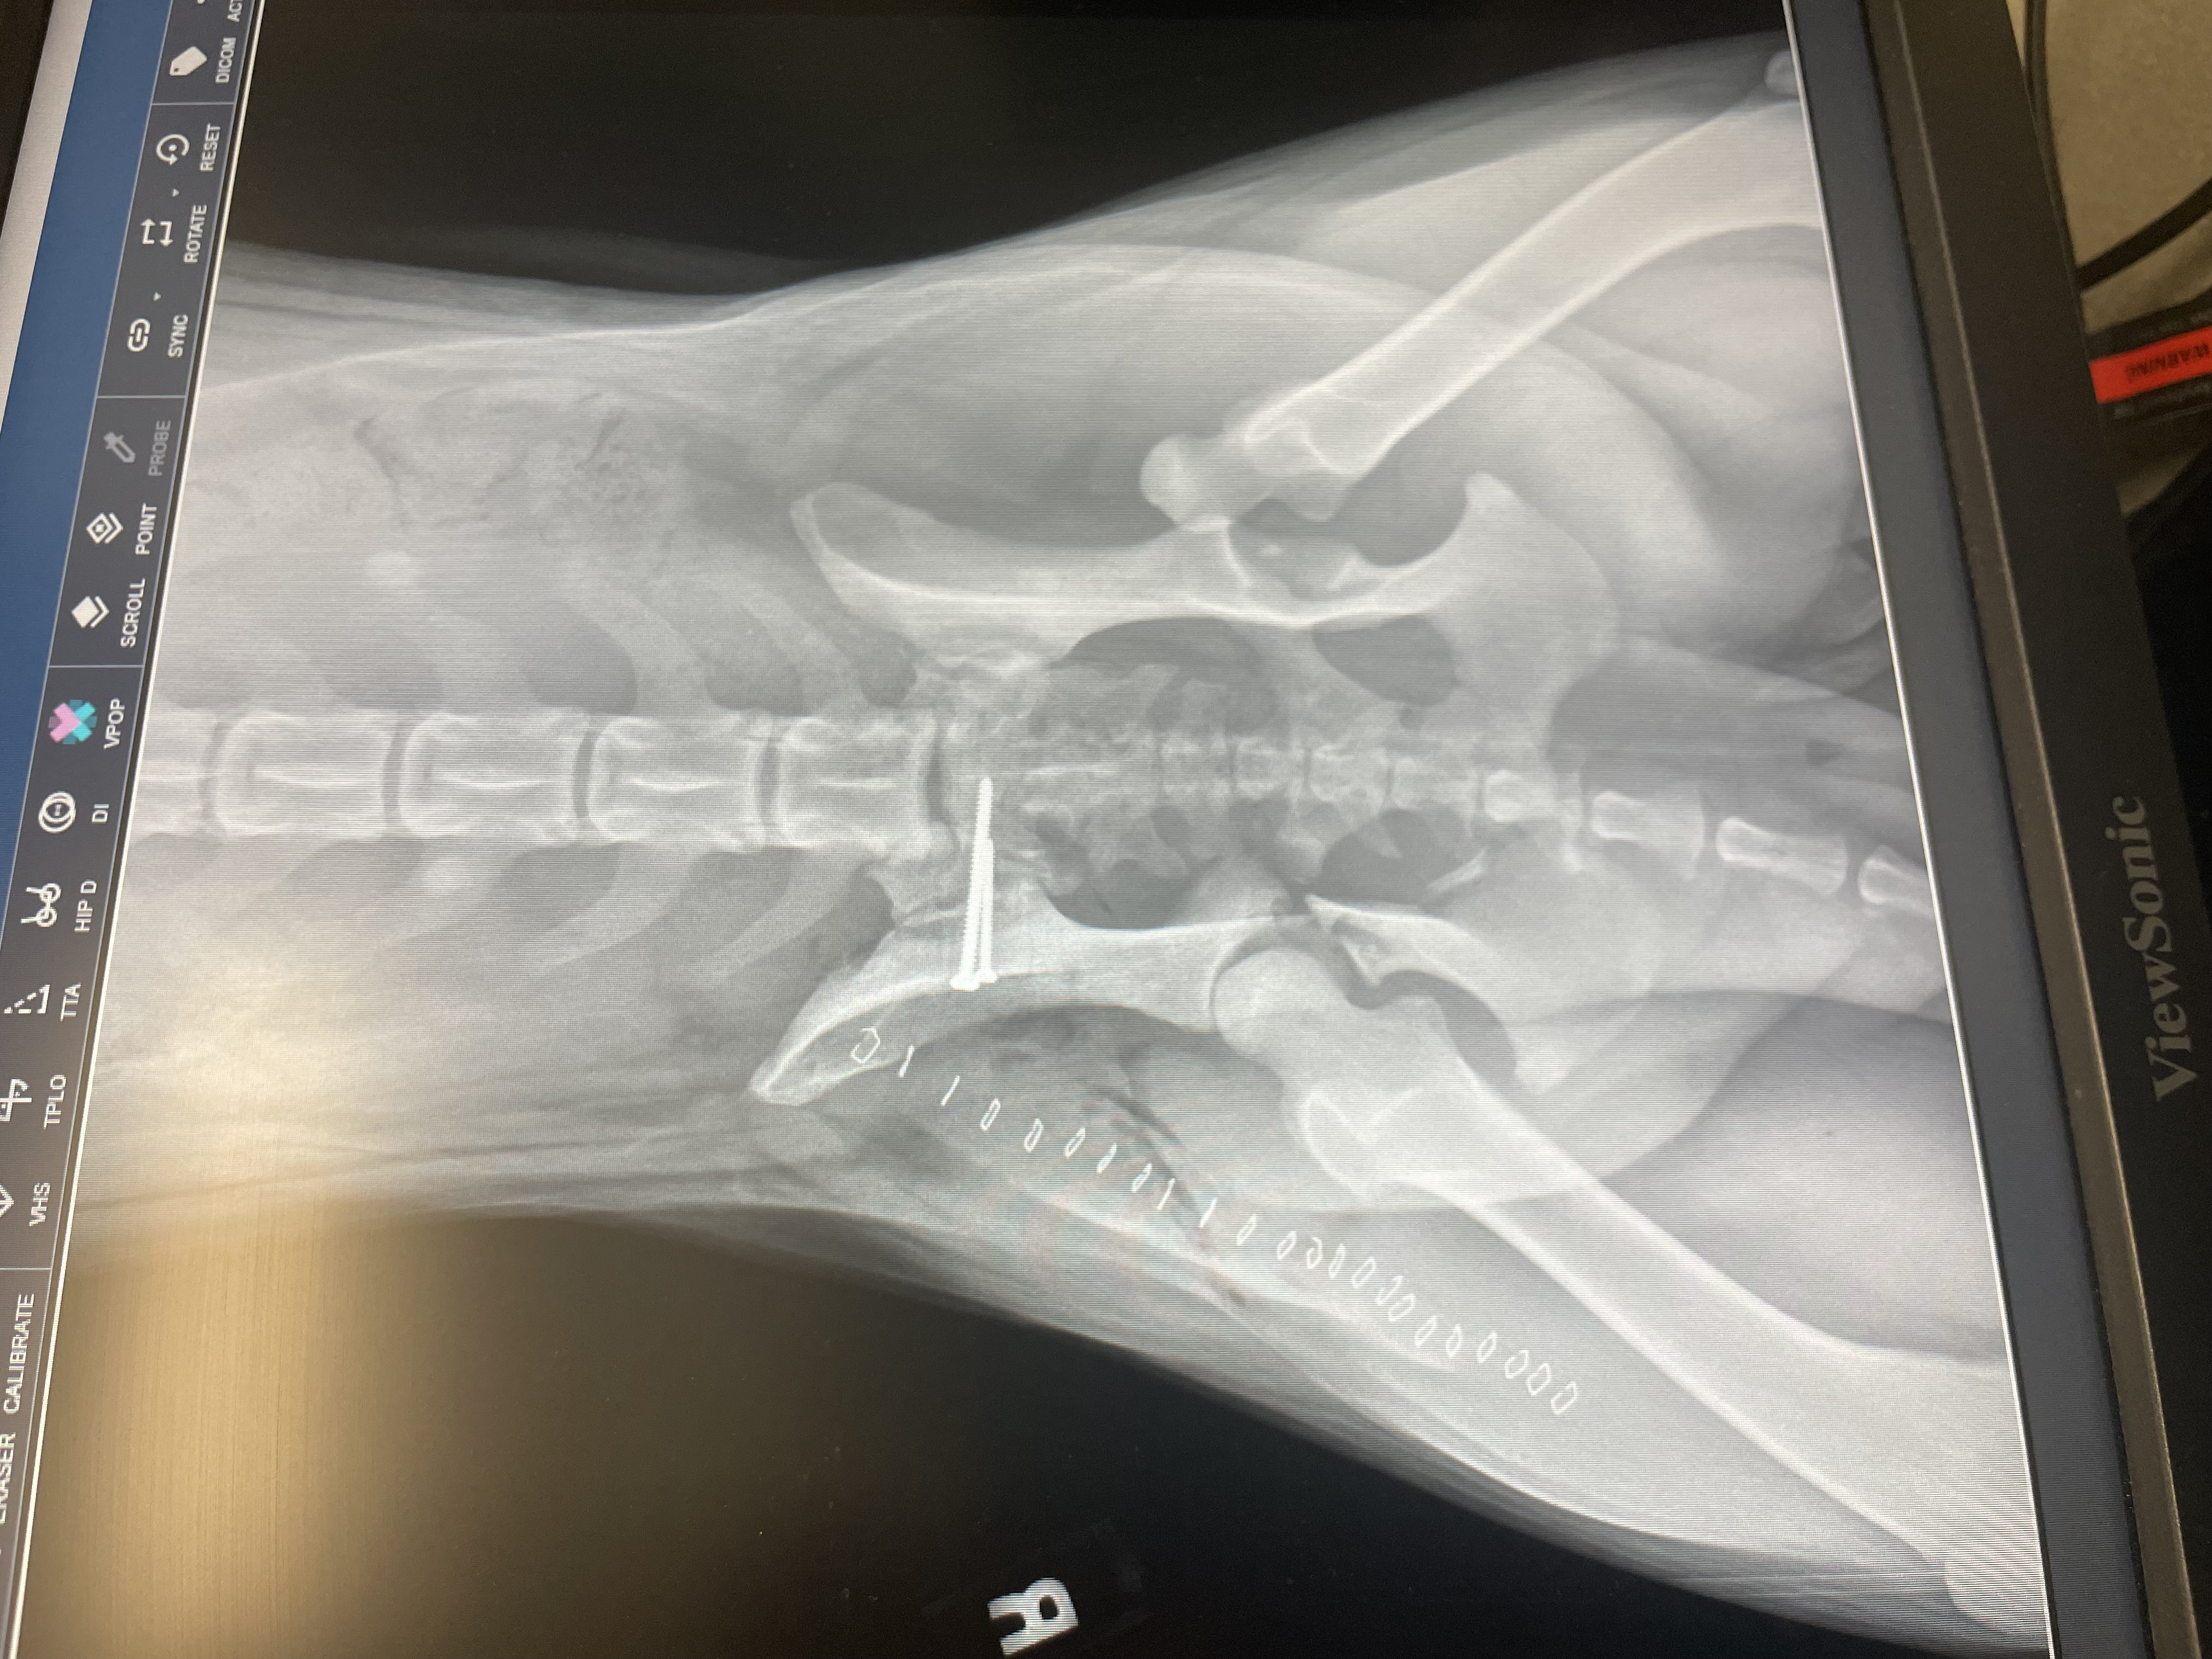

Now, for some heartwarming news: Maya's surgery was a resounding success! Dr. Sura used Fluoroscopy to locate the problematic plate in Maya's hip, a game-changer. After removing the plate, antibiotic beads were strategically placed, alleviating Maya's suffering. The decision not to use a drain this time was a relief, as it prevented the beads from being pulled out. So far, Maya has not had any swelling or discharge from the surgery.